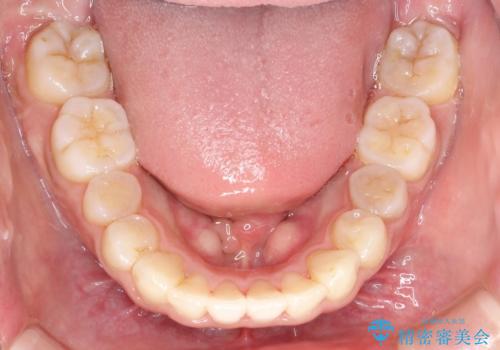

骨格的要因を背景にもつ不正咬合のため、歯列矯正単独での改善は困難と判断しましたが、患者さんとの相談の結果、歯列矯正単独で可能なところまで一緒に頑張りましょうということで、治療をすすめました。

シビアな叢生や開咬も改善することができ、想像以上の改善に時間をかけた甲斐があったと満足していただけました。